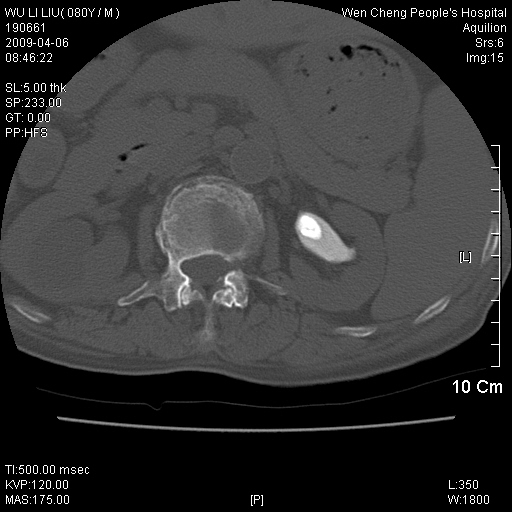

以下是引用zjzjr在2009-4-7 12:13:00的发言:[br]支持多发性转移瘤,右股骨颈骨折,腰椎亦有压缩性骨折.肝内胆管结石伴胆内外胆管扩张,左肾结石.

以下是引用liaoqiang在2009-4-7 8:44:00的发言:[br]考虑多发性骨髓瘤伴肝肺转移、肝内胆管结石、左肾结石、右股骨颈骨折。

以下是引用余辉在2009-4-7 8:52:00的发言:[br]椎骨及骨盆骨质疏松,骨破坏主要累及椎体,各骨破坏较广泛,各病灶边缘均较清晰锐利,血沉增快,白细胞增高.支持考虑多发骨髓瘤,建议查本尿周氏蛋白.[br]胆内胆管及左肾结石[br]右股骨颈骨折,考虑病理性